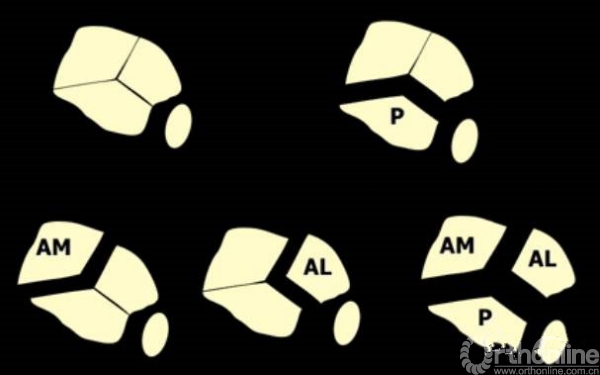

cole在2013年jot发表的文章描述了pilon骨折的骨折线图根据多例病例汇总到一起,颜色越深则越骨折线经过的可能性越大。

他将pilon骨折大致的骨块进行了分类,分别为后、前内、前外三个骨折块。

Pilon骨折的入路一共有5个,前内、前正中、前外、后内、后外。